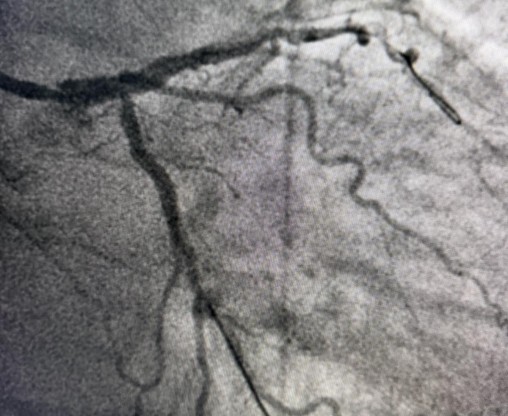

Tokom dva dana u angio sali izvedene su i izuzetno složene intervencije na koronarnim arterijama srca, uključujući perkutane intervencije na hronično - potpuno zapušenim krvnim sudovima srca i intervencije na tzv. glavnom stablu (left main) koja je glavna artrija srca i čije liječenje takođe spada u veoma rizične zahvate u interventnoj kardiologiji.

Još jedan slučaj koji izdvajamo kao posebno složen je bio kod pacijenta O.M (81), kod kojeg je dijagnostikovana teška trosudovna koronarna bolest.

„Pacijent je imao simptome angine pectoris. Nakon urađene koronarografije verifikovana je teška trosudovna koronarna bolest, gdje su bolesne bile desna koronarna arterija, dok je na lijevoj strani kritično mjesto bilo na glavnom stablu  odakle ide račvanje u dvije grane. Takvi pacijenti uglavnom završavaju na kardiohirurškom konzilijumu i na operaciji bajpasevima. Međutim, odluka konzilijuma u Banjaluci je bila da se, zbog godina života pacijenta,  radi perkutana intervencija na desnoj i lijevoj koronarnoj arteriji uključujući glavno stablo.Takve procedure zahtijevaju da se rade sa kontrolom imidžinga, savremene intravaskularne dijagnostike (IVUS), što smo mi i uradili. To dodatno povećava bezbijednost i preciznost zahvata. Procedura je trajala svega 45 minuta, a pacijent je već narednog dana otpušten kući“, izjavio je dr Janjičić.

Tim interventnih kardiologa JZU Bolnica „Sveti Vračevi“ Bijeljina je od 2020. godine izveo više od 100 intervencija na glavnom stablu (left main).